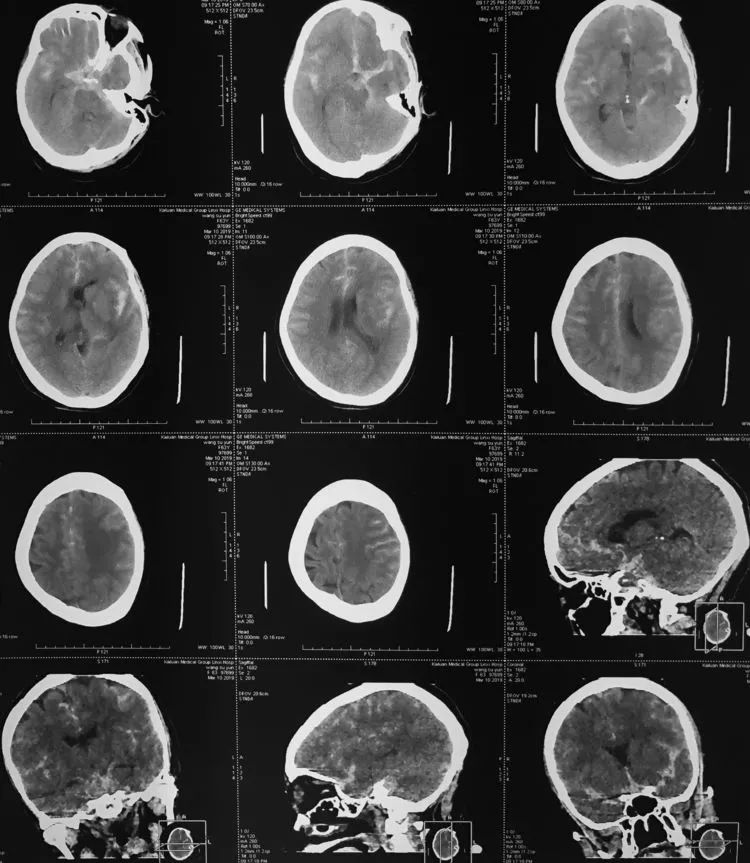

例1,男,50岁,因突发头痛伴恶心、呕吐12小时于2017年4月3日收入院。查体:颈强三横指,余无阳性体征。头颅CT(2017年4月2日)示SAH:

例2,女,61岁,因突发意识障碍18小时于2019年3月11日收入院。糖尿病、冠心病病史10余年。查体:神志恍惚,躁动,GCS 11分。双瞳孔等大等圆,光反应灵敏,颈抵抗,四肢肌力检查不合作,双侧病理征未引出。头颅CT(2019年3月10日)示SAH: